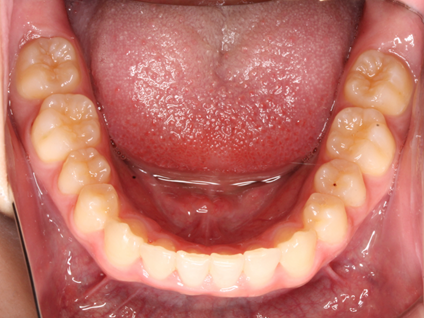

一般的な矯正治療は歯の全体に矯正装置をつけて、噛み合わせなどを改善しながら歯を移動させますが、部分矯正は前歯を中心に一部分の歯のみを動かしていきます。

ワイヤー矯正では気になる歯の部分にのみに矯正装置を装着して治療を行い、マウスピース矯正は歯の形にそって歯並びを治していきます。